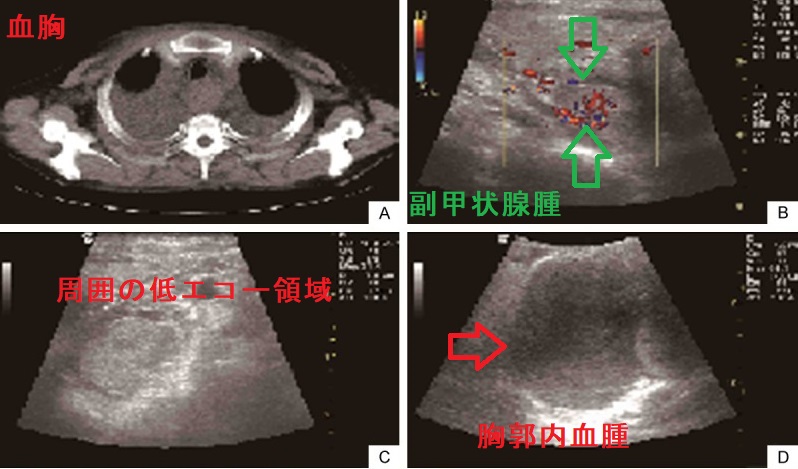

副甲状腺腺腫の自然破裂による出血で血腫が生じ、呼吸困難になる事があります。甲状腺超音波(エコー)検査では、甲状腺および副甲状腺腺腫の周囲に出血による低エコー領域を認めます。報告例では、血胸、縦隔血腫があるものの、呼吸状態が悪くなかったので、気管内挿管を行わず経過観察になりました。(Int J Clin Exp Med. 2015 Nov 15;8(11):21826-9.)

しかし、

- 呼吸困難・気管圧排があれば、ためらわず気管内挿管と血腫除去

- 首の腫れと、貧血が徐々に悪化すれば(要するに出血が止まらない)、血腫除去

が必要と筆者は考えます。

同様の出血を来す甲状腺動脈瘤破裂で命の危険との鑑別も必要です。

胸部異所性副甲状腺腫の出血は、縦隔血腫による血胸を生じ、胸痛、咳、呼吸困難になります(Acta Otolaryngol Suppl. 2007 Dec;(559):160-3.)。